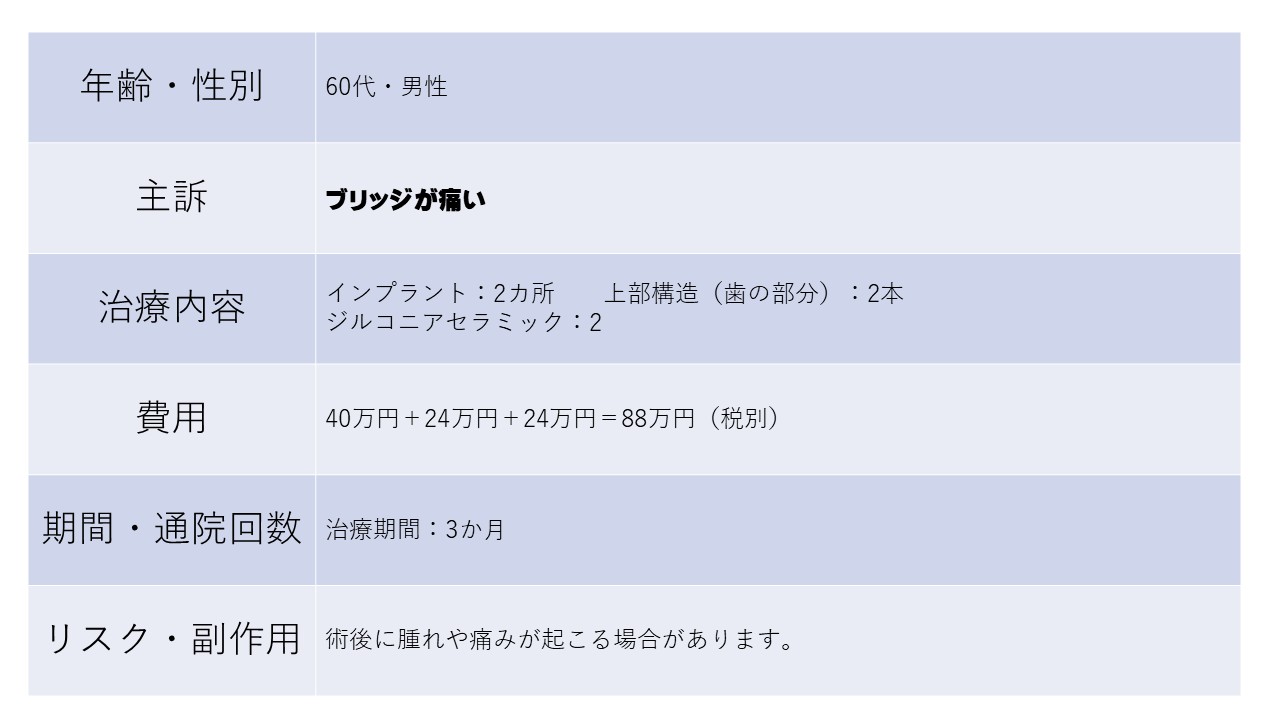

ブリッジが痛い 60代 男性ーインプラントー

ブリッジが痛い

ブリッジがグラついて咬めなくなり抜歯して

インプラントを入れた。

元々奥に1本入っていたインプラントを利用して

インプラントブリッジにできた。

インプラントを入れておいて良かった。よくかめる。

インプラント 手術代 1ヶ所:20万円×2

上部構造(歯の部分) 1本:12万円×2

ジルコニアセラミック 1本:12万円×2

20万円×2ヶ所+12万円×2本+12万円×2本

=88万円(税別)